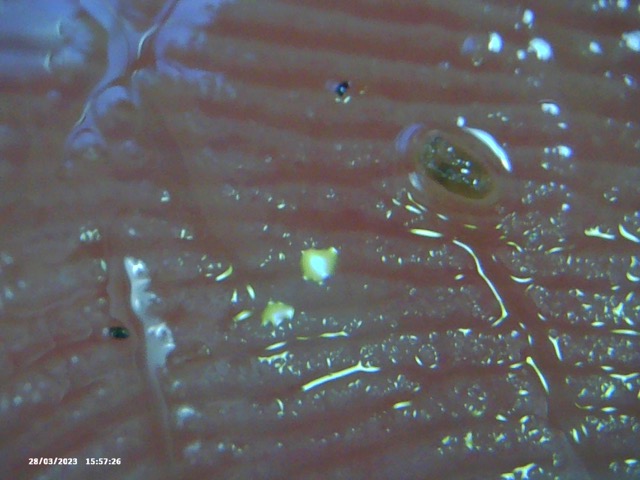

I showed him what I thought were reasonable compelling pictures of something that is clearly not right.

So I feel movement on parts of my body, then I get slight lumps and then I get these extremely large and sore white spots … and also, if I massage oil into those lumps I remove these objects.

So what are these objects with black things in?

‘Buried in the skin, and encased in these really hard objects that I’m extracting?’

Below is the selection of recent images that I showed him. In isolation they look like they could be ‘anything’ – but with the context of my described condition, and the consistency of objects being extracted, I thought this might, at a minimum be considered ‘not right’ and warrenting further investigation. Silly me.

Image Notes:

- That is my fingerprint in the background.

- All objects are recent and have been extracted over the last 2 weeks

- I simply cannot see some of these objects – however I can feel them, ROCK HARD.

- ‘Hair’ included for a sense of scale and also to help counter the lazy argument ‘That could be Hair embedded in those objects’ – mental gymnastics.

- This is a small selection of what I’m taking out of my skin where I am feeling movement, there are literally 100’s of these things. Imaging them become’s pointless as they are similar.

- Average Distance between fingerprint ridges is 0.15mm for a sense of scale.